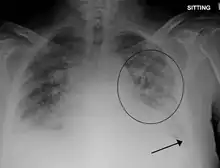

- Acute or worsening respiratory distress (tachypnea, dyspnea, cyanosis, and/or hypoxemia) in the absence of other causes

- Evidence of acute or worsening pulmonary edema (by physical examination or chest imaging)